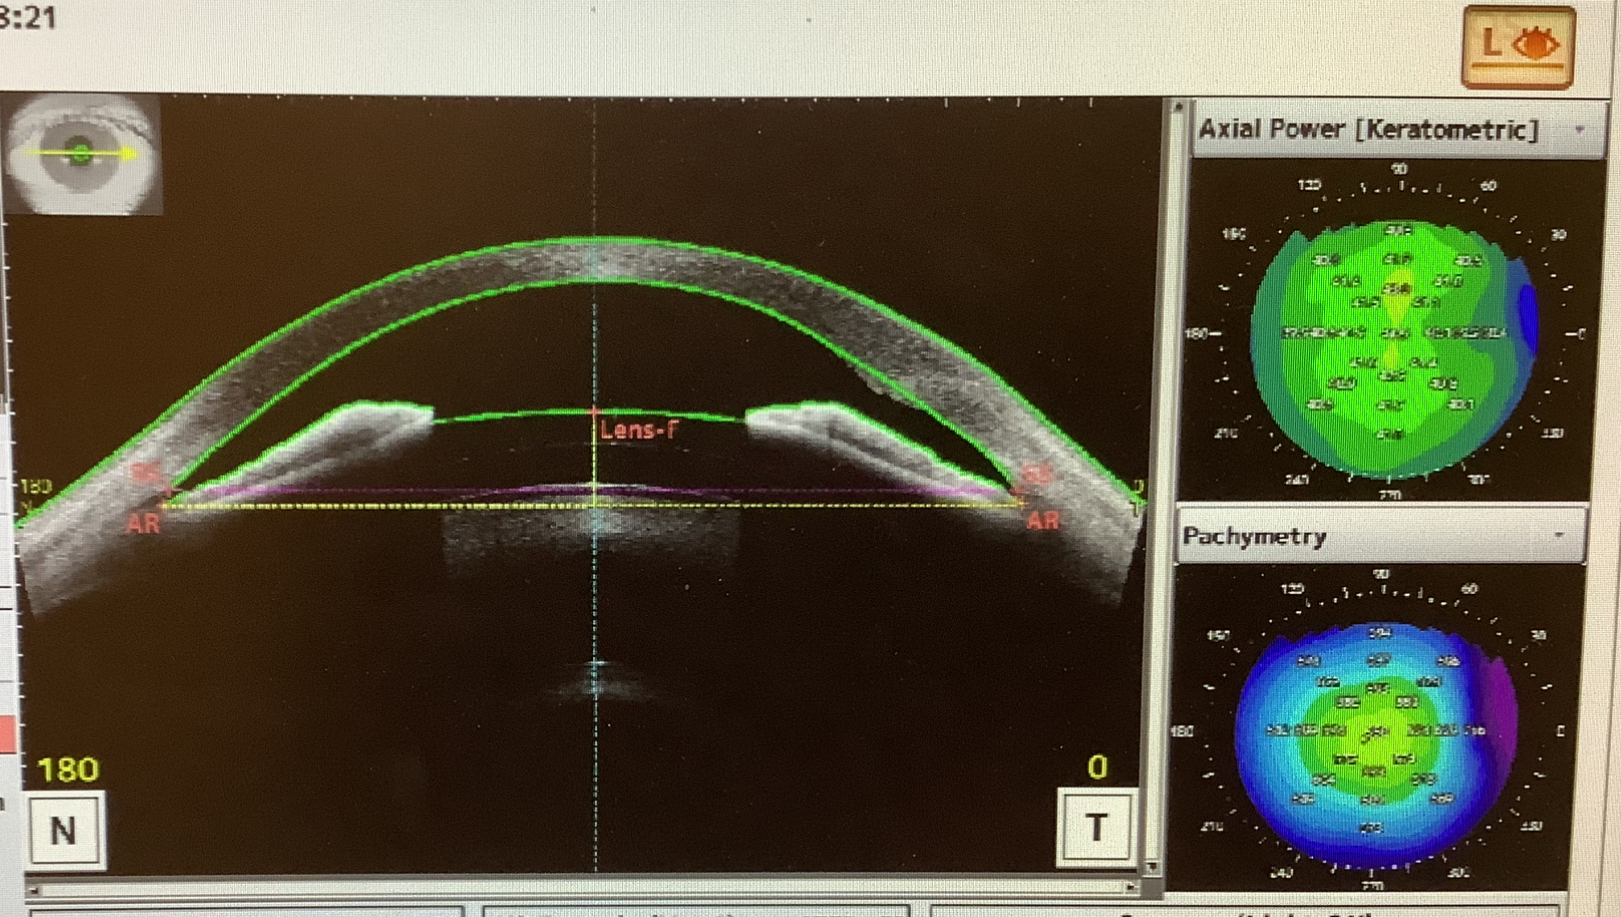

ICL手術の患者さまは、眼に入れたレンズの位置が上過ぎると虹彩を押してしまって眼圧を上げてしまい、下過ぎると水晶体に触れてしまって白内障が出てしまうので、

その位置はとても重要なので手術終了後すぐに前眼部OCT(CASIAⅡ)で一度、確認し、手術翌日の今日も再度、確認させていただいています。レンズの位置も大丈夫で、キズもきれいにくっついていて、全く問題ありませんでした。

このCASIAⅡの検査の写真を見て、思ったのですが、術後の患者さまからよく聞かれる『顔を洗った時に眼に水が入るとダメですか?』という質問の“眼の中”ってどこ?という話です。多分、皆さまの言う眼の中というのは、眼の表面のことなのかなと思います。本当の眼の中というのは、角膜よりも眼の内側で完全に外と区切られた内部のことが、厳密な“眼の中(眼内)”ということになります。患者さまからしたら、眼の表面でも眼の中でも関係ないかもしれませんが、眼の表面がきれいかというと、実際は眼の外なので、完全にきれいという訳ではありません。ここで言う“きれいではない“ということの意味は、細菌がいるという意味で、手の皮膚の表面と同じで通常は病気を起こすことのない常在細菌がいる訳です。ですので、時々、術後間もない時期に顔を洗う時などに『眼に水が入ってしまった』と心配して受診される方もいらっしゃいますが、そもそも、眼の表面は眼の外なので基本的には問題ないと考えています。ただ、術直後はまだキズが完全にくっついていないので、強く眼が圧迫されるとキズが開いてしまう可能性もあるので、眼を強く押してしまうような動作は注意が必要かと思います。